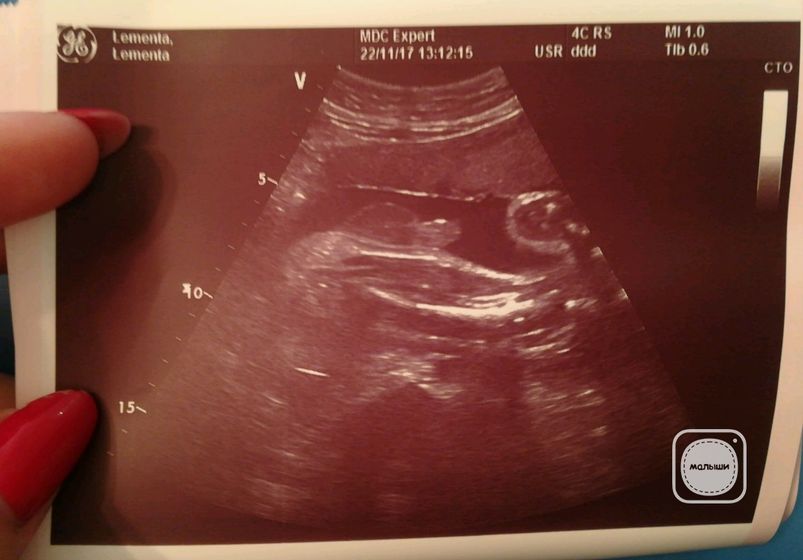

Недавно ходила на третий скрининг. У нас всё отлично. Весим 1680 +-250гр. Сыночек хорошо нам позировал. Показал нам класс?? И всё время показывал своё достоинство, скромностью не страдает. Весь в папу? В подарок нам сделали фоточку нашего мужского достоинства.? Не могу уже дождаться нашей встречи. Осталось совсем чуть чуть ??

Снимок с УЗИ такой интересный )

Ага? Это писюнок?